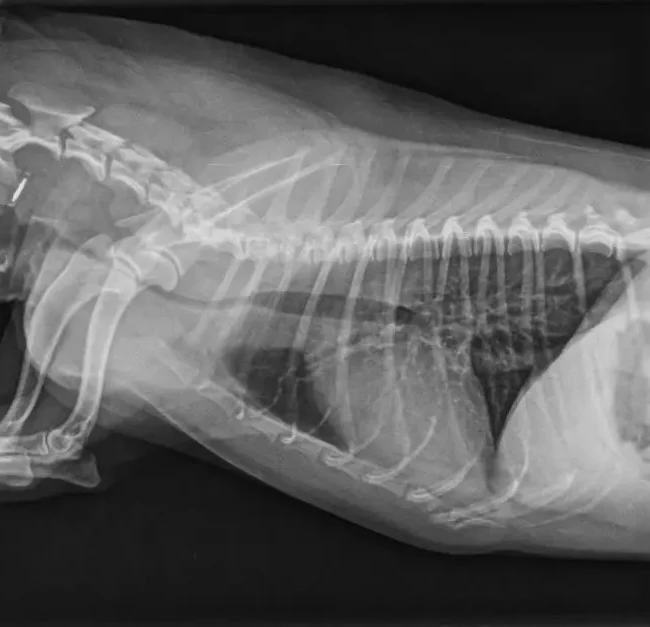

Cuando hay una ruptura o defecto en el diafragma, la presión negativa intratorácica favorece que los órganos abdominales pasen hacia la cavidad torácica.